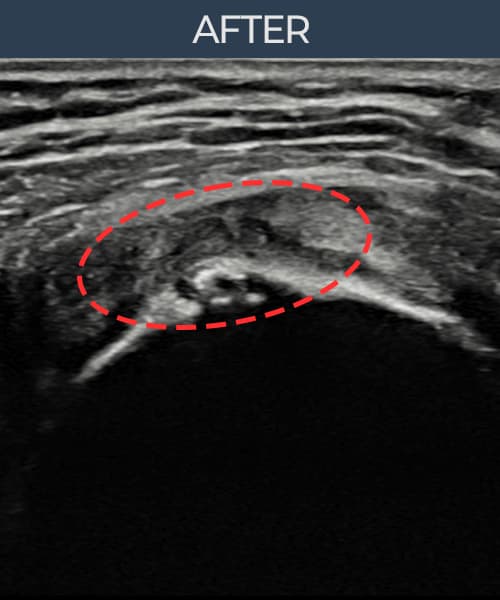

超声确认旋转肌腱袖 关节面侧撕裂(9mm × 5mm (肌腱厚度约50%缺损))。缩小缝合术后肌腱连续性恢复,患者回归正常生活。

术后

术前超声确认旋转肌腱袖 关节面侧撕裂,冈上肌腱回声不连续伴肌腱缺损(9mm × 5mm (肌腱厚度约50%缺损))。术后超声显示撕裂部位充满再生组织,肌腱连续性恢复,回声模式正常化。

该患者持续肩痛。详细超声检查确认旋转肌腱袖 关节面侧撕裂(缺损:9mm × 5mm (肌腱厚度约50%缺损))。在超声引导下实施非手术缩小缝合术。术后佩戴支具约4-6周,随后进行分阶段康复锻炼。随访超声确认肌腱连续性恢复、结构稳定,患者顺利回归日常生活。